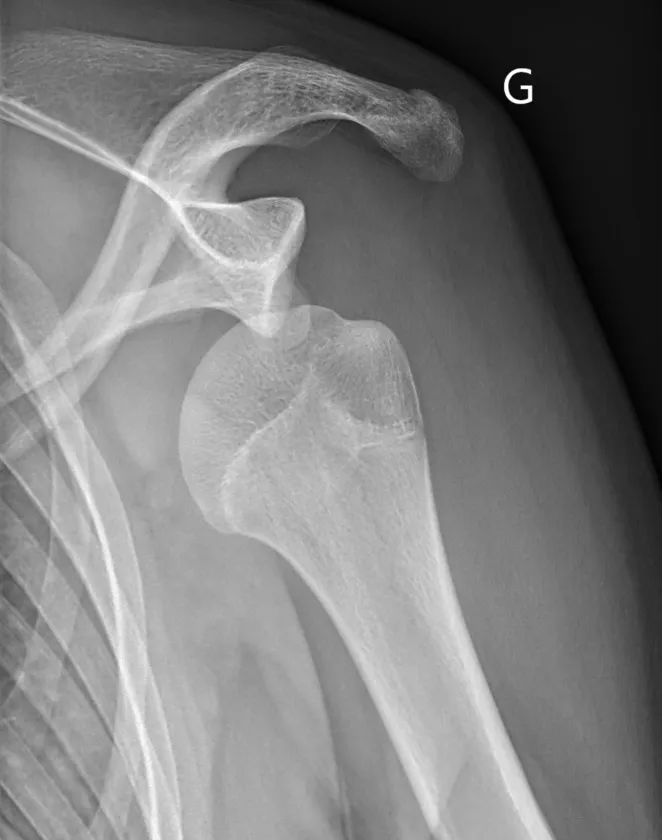

- Radiographies — bilan de débrouillage, recherche de lésions osseuses associées

Les lésions osseuses

- Fracture du rebord glénoïdien — la tête humérale heurte violemment la glène et en arrache un fragment. Quand cette perte osseuse est importante, les techniques arthroscopiques seules ne suffisent plus.

- Encoche de Hill-Sachs — la tête humérale s'écrase contre la glène comme une balle de ping-pong qu'on écraserait avec le doigt. Cette déformation est irréversible.